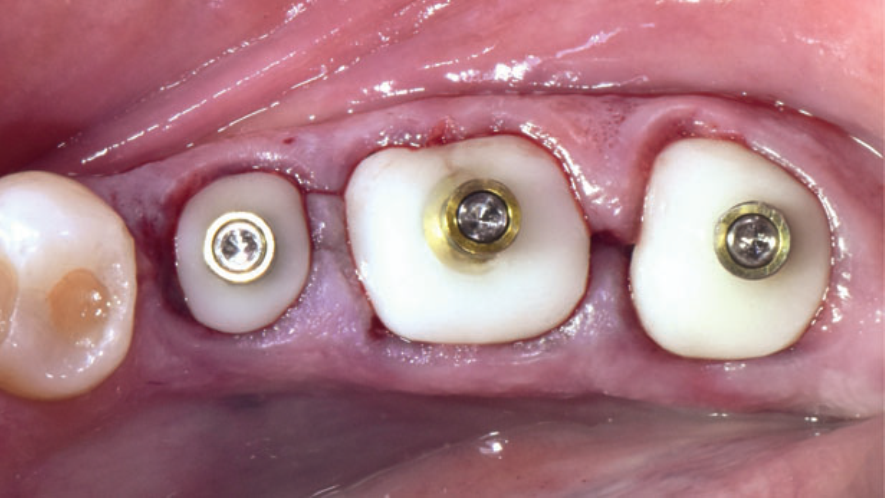

A restauração protética esteticamente agradável de um implante requer a criação de um adequado perfil de emergência da mucosa peri-implantar, que é a transição entre o implante e a coroa protética. Quando corretamente explorado, proporciona uma suave transição da plataforma circular do implante para a anatomia natural do dente. Quanto mais detalhados forem estes processos, maiores serão as chances de sucesso dos tratamentos protéticos reabilitadores.

Ao serem instalados, os implantes que atingem um torque de inserção ≥ 32 Ncm podem ser imediatamente carregados com coroas unitárias de transição não oclusivas. Abaixo deste torque, ou em situações onde não desejamos correr riscos, em vez de uma coroa de transição, instala-se um cicatrizador personalizado contendo um perfil transmucoso com as mesmas características que a coroa provisória teria. Os objetivos dos cicatrizadores customizados nos casos de instalação do implante imediatamente após a exodontia são: selar o sítio cirúrgico respeitando o perfil do alvéolo de extração, estabilizar o coágulo sanguíneo e favorecer a regeneração óssea com o material substituto, evitar o colapso de tecidos moles durante o período de cicatrização e desenvolver um perfil de emergência protético ideal para a futura coroa sobre implante, baseado na anatomia do dente natural extraído, sem receber carga oclusiva.

Nos casos de instalação de implantes em regiões edêntulas, também é possível empregar cicatrizadores personalizados, desenvolvendo um perfil de emergência protético ideal para a futura coroa sobre implante, baseado na anatomia do dente natural ausente. Os dois procedimentos restabelecerão o perfil de emergência original do paciente durante a fase de cicatrização/osseointegração dos implantes, devolvendo a harmonia dentogengival, com a recuperação das papilas interdentais e a reconstituição do arco gengival côncavo, com altura adequada da margem em relação aos dentes adjacentes.

Quando corretamente indicados e executados, os cicatrizadores personalizados proporcionam bons resultados estéticos, biológicos e funcionais. A criação/manutenção de um perfil de emergência anatomicamente correto é um dos aspectos mais importantes para fornecer resultados estéticos e funcionais agradáveis às próteses implantossuportadas, tanto no setor anterior quanto no setor posterior.